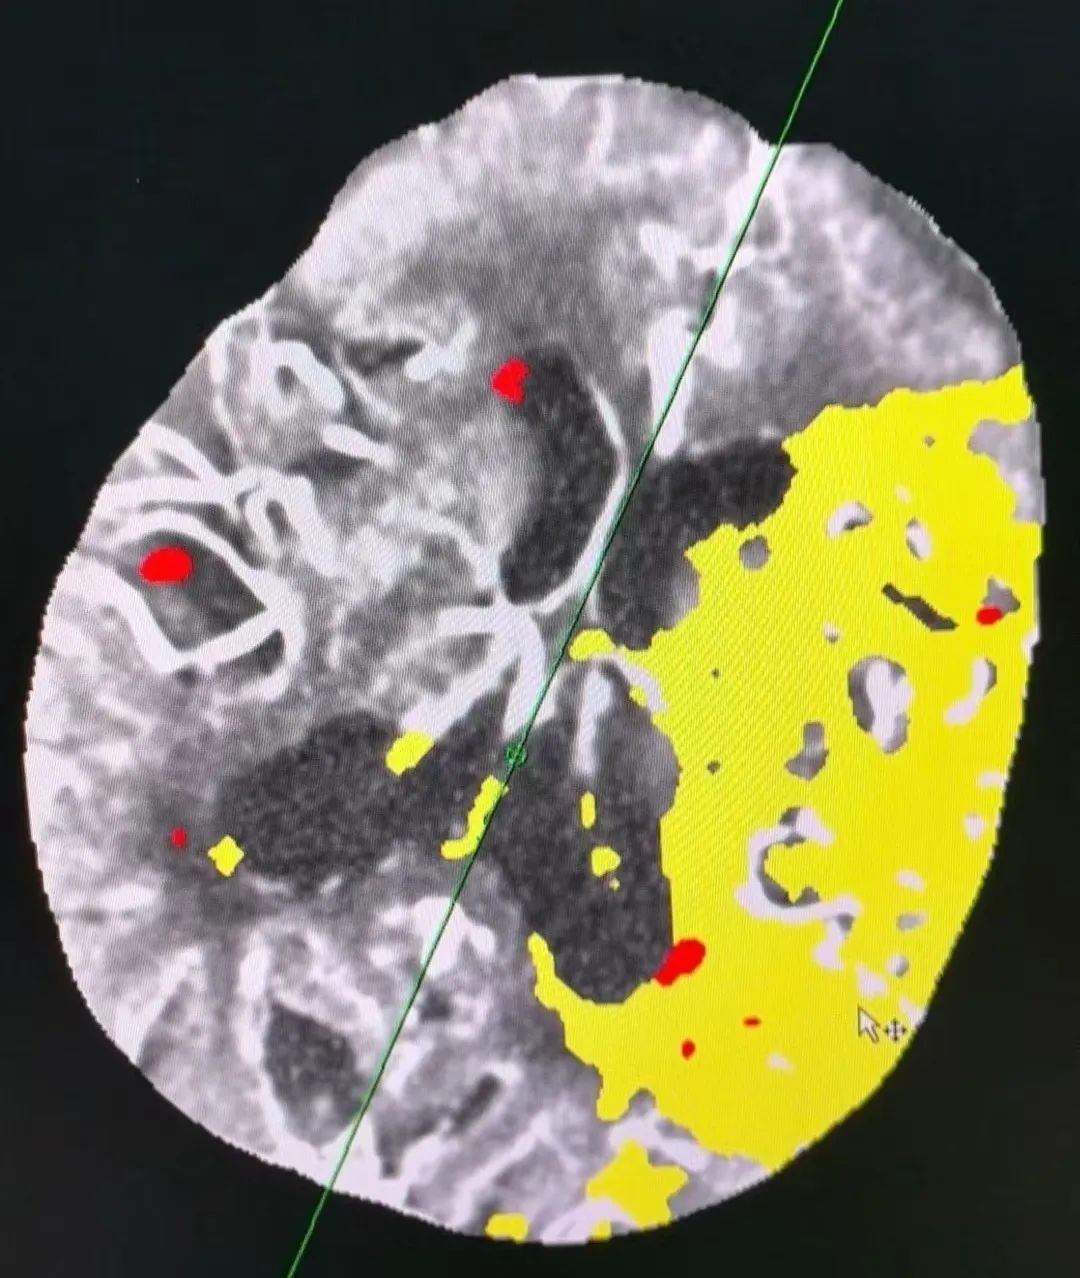

到院后,行高级影像评估检查显示:

陈大爷左侧颈内动脉完全闭塞,左侧大脑中动脉串联栓塞,更令人震惊的是血管内竟嵌顿着 9 枚血栓!这相当于常规取栓手术 4-5 倍的工作量, 对于百岁老人脆弱的血管堪称生死考验。